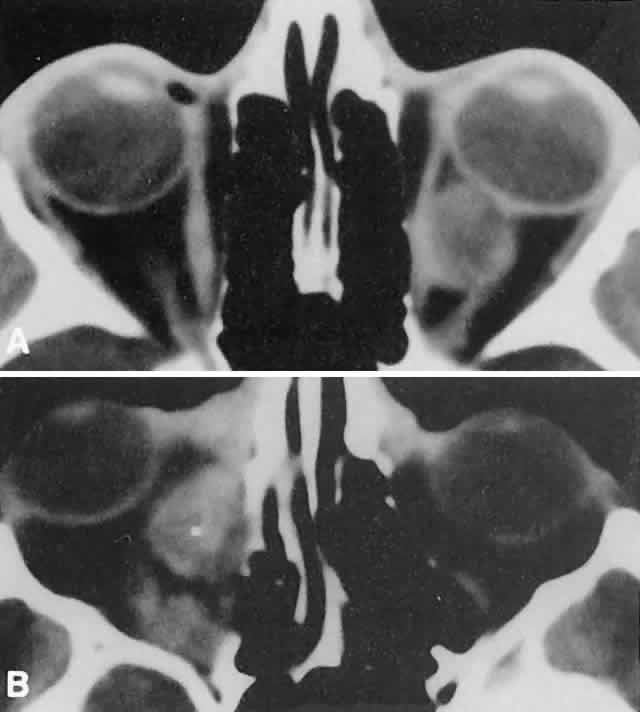

Acute blood cyst formation in this age group makes the distinction between a pre-existent but clinically silent lymphangioma and a rapidly emerging rhabdomyosarcoma a common orbital diagnostic problem. Evidence suggesting an orbitallymphangioma includes the variable finding of conjunctival or eyelid components of the malformation.86 Conjunctival lesions appear as ectatic channels filled with clear or hemorrhagic fluid. Eyelid ecchymosis may result from the seepage of blood out of the thin-walled orbital cysts. Additional developmental anomalies of the eye and adnexa may be present. Other head and neck involvement may be manifest as local hypertrophy (e.g., of the cheek or lips), and cystic palatal lesions may be seen. CT discloses a single or multilobulated mass, which represents only the blood cyst portion of the tumor (Fig. 14). Individual lobules may have different radiodensities depending on the presence of clots or liquefied blood within each cyst (Fig. 15). A generalized increase in orbital dimensions suggests a long-standing, probably congenital process. Echography may help differentiate the cystic components of lymphangioma from cellular rhabdomyosarcoma. Echography shows the blood cysts to be acoustically inactive spaces, with extremely low internal reflectivity (Fig. 16). Clots within the cysts can increase internal heterogeneity, however. MRI has virtually eliminated the need for diagnostic biopsy in this condition, because of its ability to show differing magnetic properties of suspended, degrading blood products (Fig. 17).